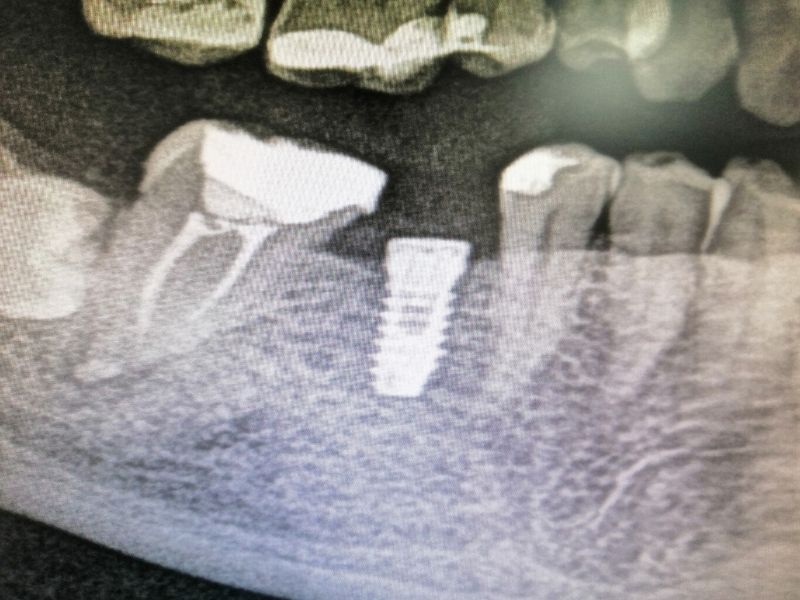

El primer paso en una situación así es realizar un estudio radiográfico para analizar la situación en el estado actual de la boca. En ese estudio pudimos observar que la mejor propuesta de tratamiento, para su caso concreto, era la colocación de implantes como vía para reponer las piezas dentales ausentes.

Tras realizar la valoración pertinente, le tomamos al paciente un registro en 3D Tac Dental (CBCT) con la finalidad de analizar y programar al detalle la colocación de los implantes. Es un paso necesario previo al comienzo del tratamiento, que nos ayuda a planificar los pasos a seguir y a determinar los plazos.